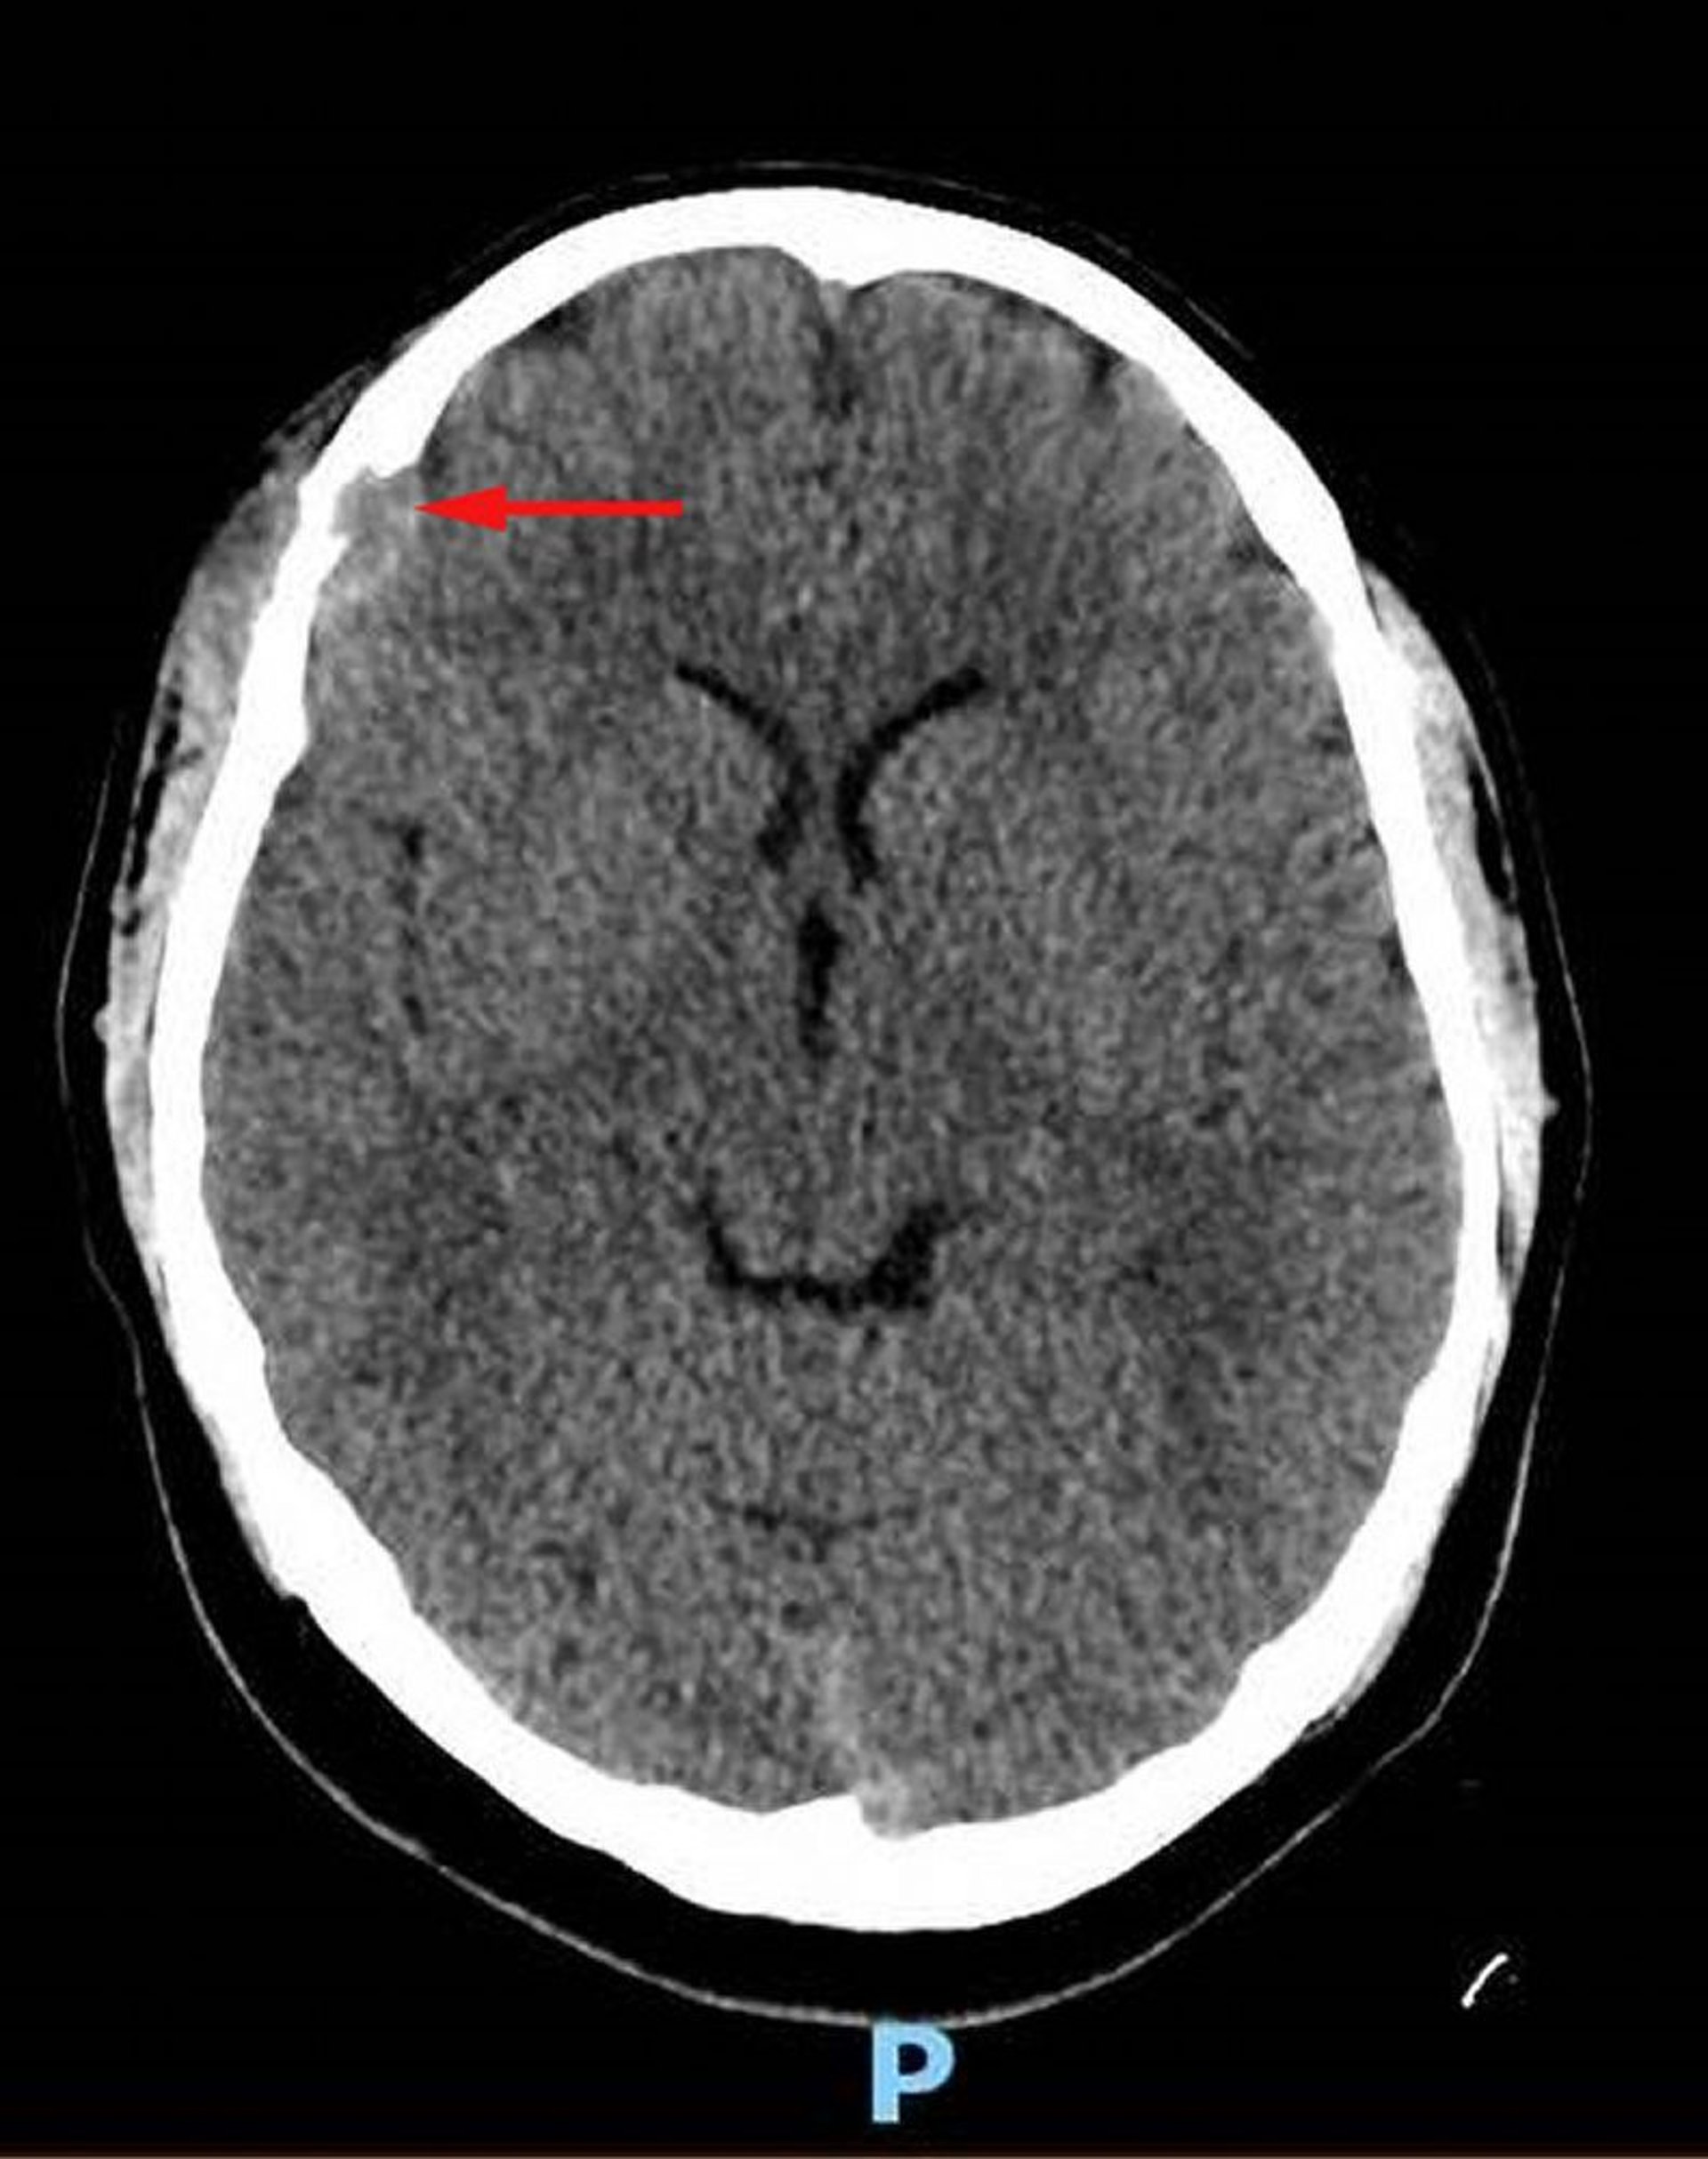

Hình ảnh này cho thấy một tổn thương mô mềm ở xương trán bên phải với sự phá hủy mô mềm liên quan và sự kéo dài nội sọ của mô mềm vào khoang màng cứng (mũi tên đỏ). Có mô mềm da đầu bên trên không đối xứng. Sinh thiết là chẩn đoán cho bệnh mô bào tế bào Langerhans.

Hình ảnh do bác sĩ Carolyn Fein Levy và bác sĩ, tiến sĩ Jeffrey M. Lipton cung cấp.